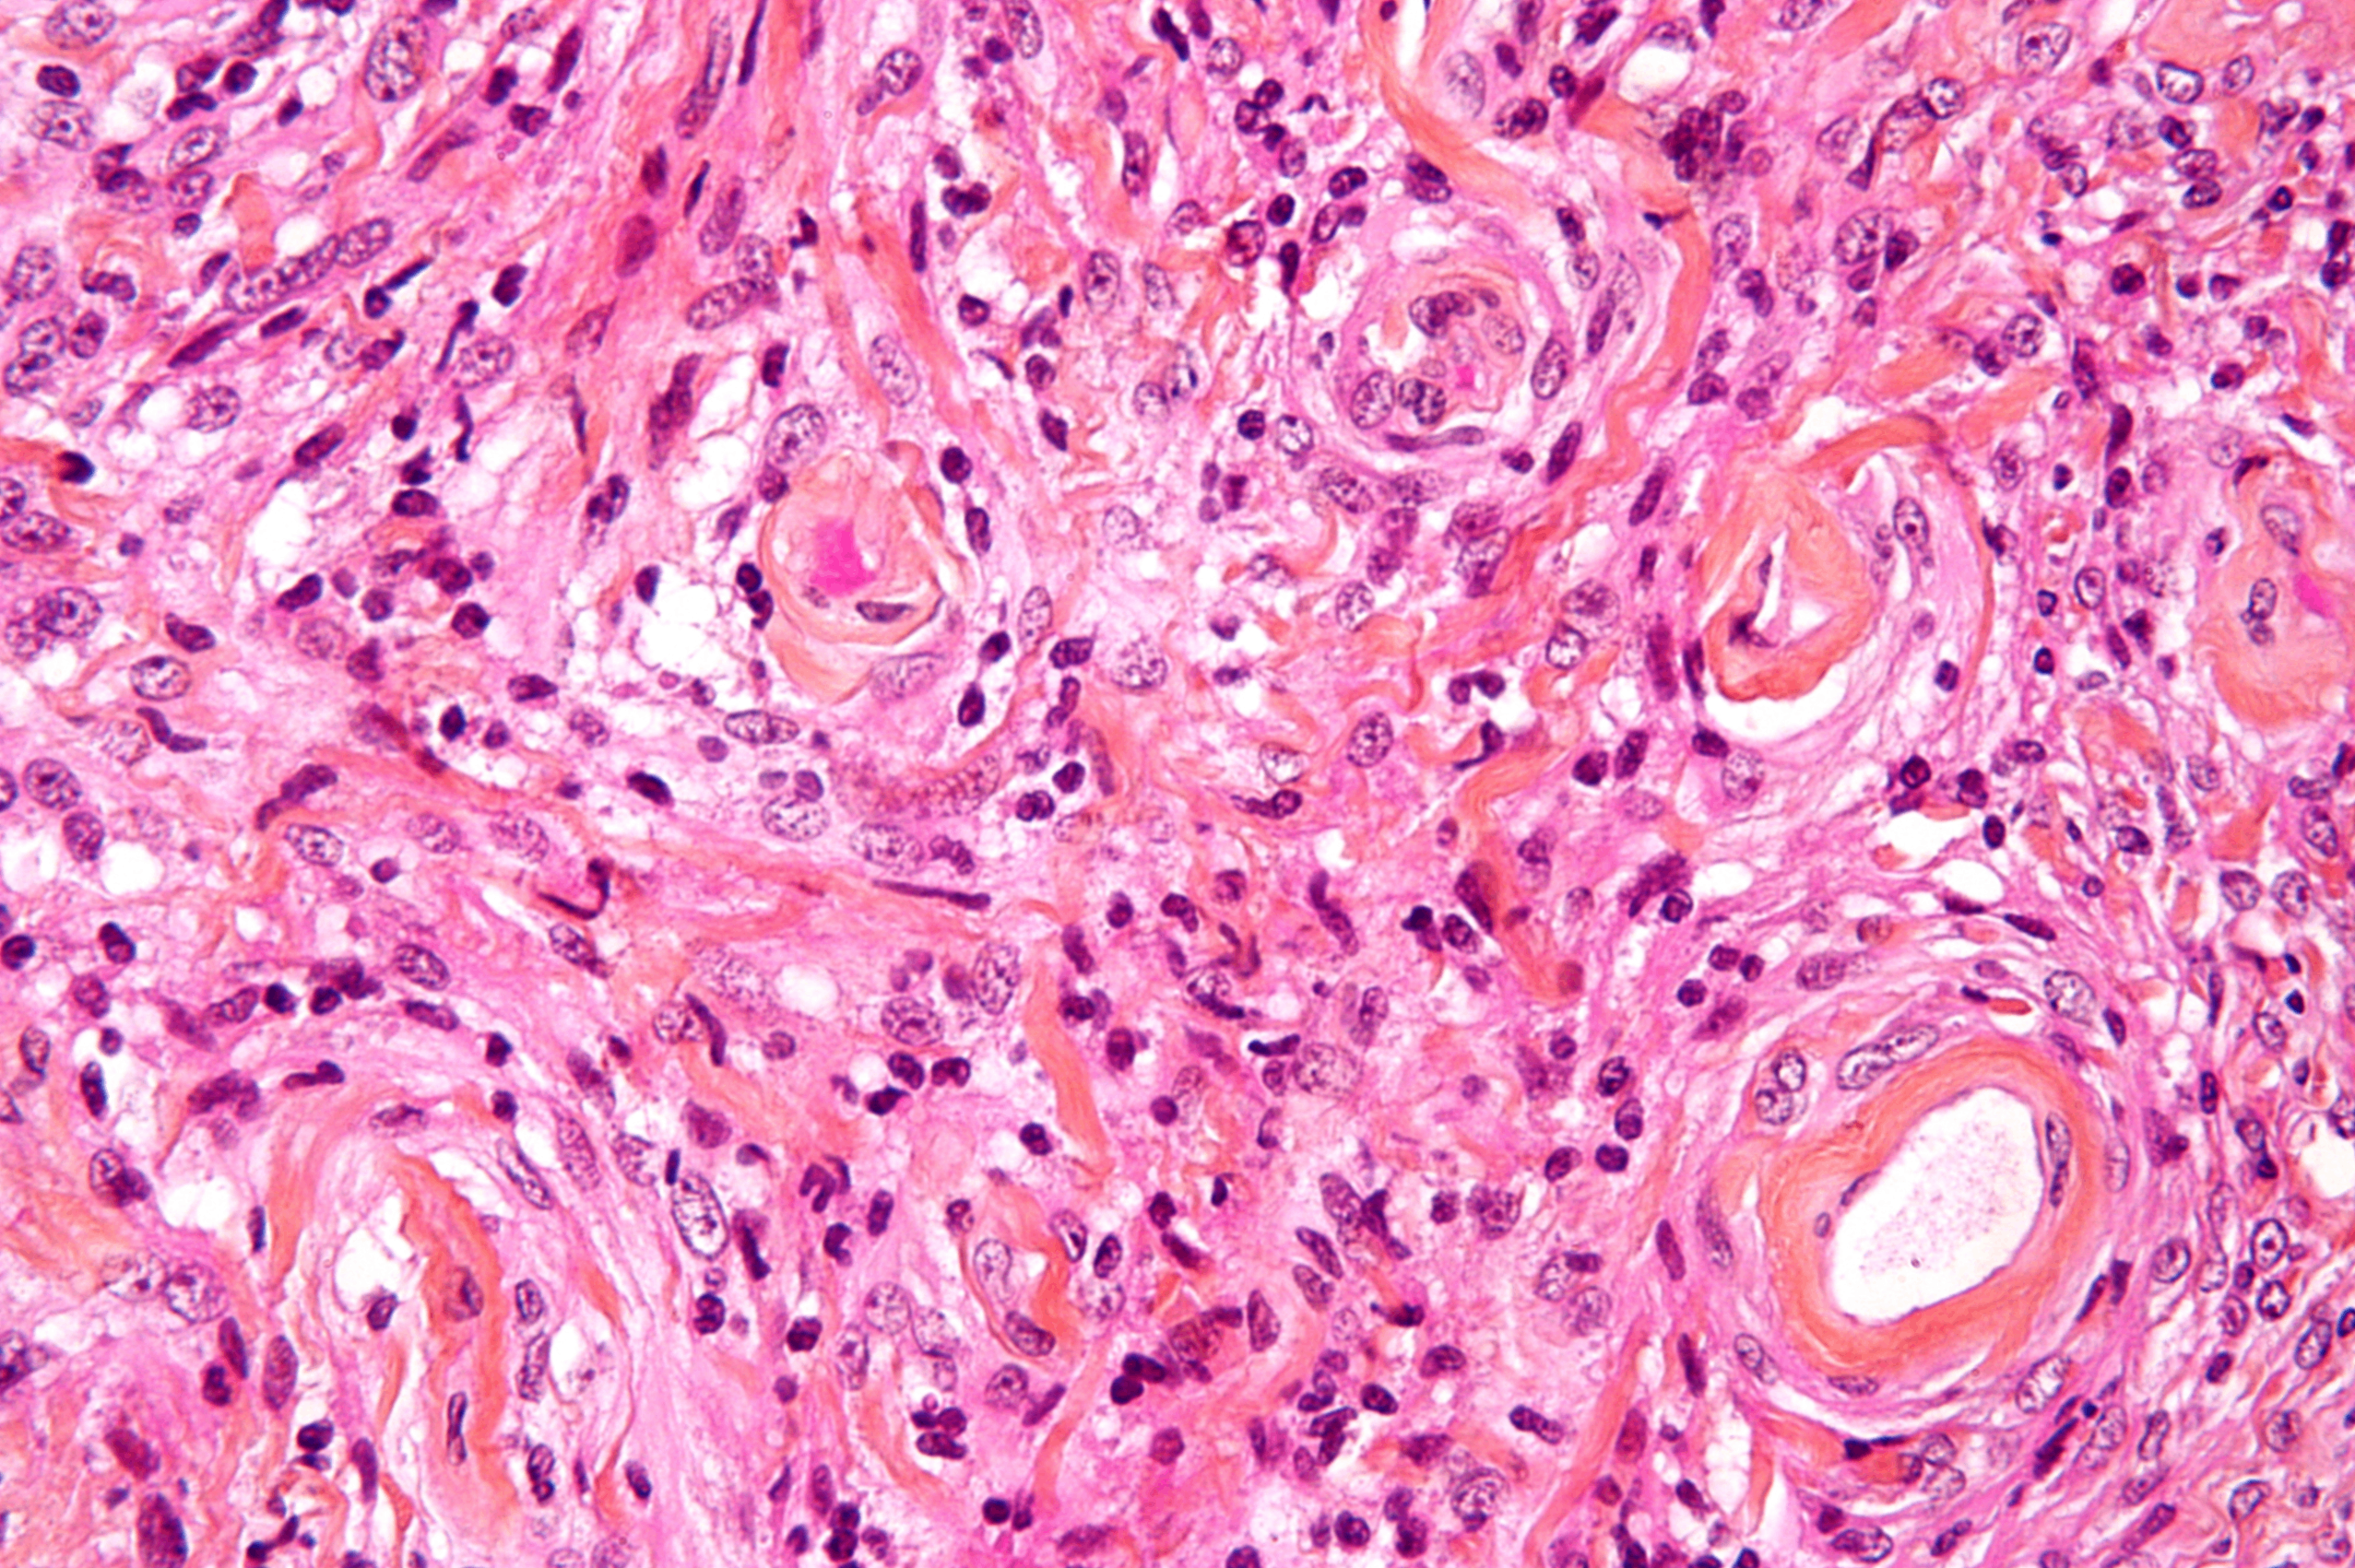

Oligodendroma, Wikimedia Commons

2) 병리소견

• 젤라틴처럼 말랑한 회색 종괴로, 내부에 낭종(cyst), 국소 출혈(focal hemorrhage), 석회화(calcification) 자주 동반됨

• 종양세포는:

- 둥근 핵과 과립상의 염색질을 가지며 맑은 공포성 세포질(clear halo of vacuolated cytoplasm)로 둘러싸임 → 이로 인해 fried egg appearance라고도 불림

- chicken-wire 형태의 가는 모세혈관 네트워크가 전형적으로 관찰됨